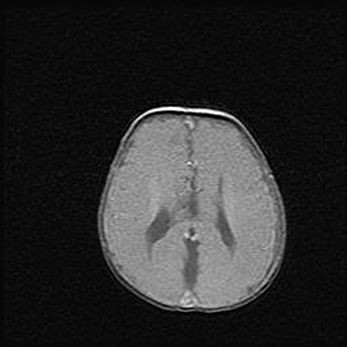

Наружная гидроцефалия с возможной атрофией височных областей.

Возраст: 28 дней

Вес: 3670 г

Пол: мужской

Окружность головы: 38 см

Срок гестации: 40 недель

Гидроцефалия головного мозга у новорожденных – это заболевание, которое характеризуется скоплением избыточного количества спинномозговой жидкости в желудочковой системе головного мозга в результате затруднения её перемещения от места выработки к месту поглощения в кровеносную систему или вследствие нарушения абсорбции. При открытой наружной форме гидроцефалии у новорожденных расширяются и переполняются субарахноидные пространства.

При нормотензивных  формах,  которые,  как  правило,  являются  следствием  перенесенных ишемических  повреждений  паренхимы  мозга,  возможно  сочетание микроцефалии  с нормотензивной гидроцефалией. В основе данных изменений лежит атрофия больших полушарий с преимущественной  локализацией  в  лобно-височных  областях.